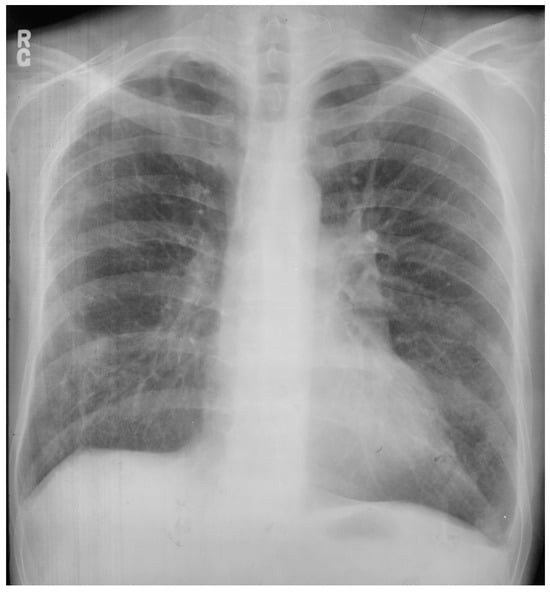

Posteroanterior chest X-ray of coarctation of the aorta: This is the chest X-ray of a 21-year-old male college student who presented for evaluation of hypertension. He spent most of his time studying, because he did not excel in sports due to cramping in his legs when he would run. The blood pressure was 170/80 mmHg in the right upper extremity and there was a marked brachial artery–femoral artery delay when simultaneously palpated. There was a grade 2–3/6 decrescendo diastolic murmur of aortic regurgitation. In the left upper posterior chest there was a long systolic murmur across the coarctation. This chest X-ray is well centered and there is a good inspiration. The cardiothoracic ratio was at the upper limits of normal and there is straightening of the left heart border, due to left ventricular volume overload from severe aortic regurgitation and left ventricular hypertrophy from his coarctation. There is rib notching of the undersides of ribs 4–8 bilaterally (indicated by four blue dots) from enlarged and coiled intercostal arteries carrying collateral blood flow. There is no three-sign, perhaps because this is not an anteroposterior film. He went on to have surgical repair of the coarctation via left lateral thoracotomy and then aortic valve replacement via median sternotomy for a bicuspid aortic valve with severe regurgitation. His blood pressure and his heart size both decreased and his tolerance for exertion improved.